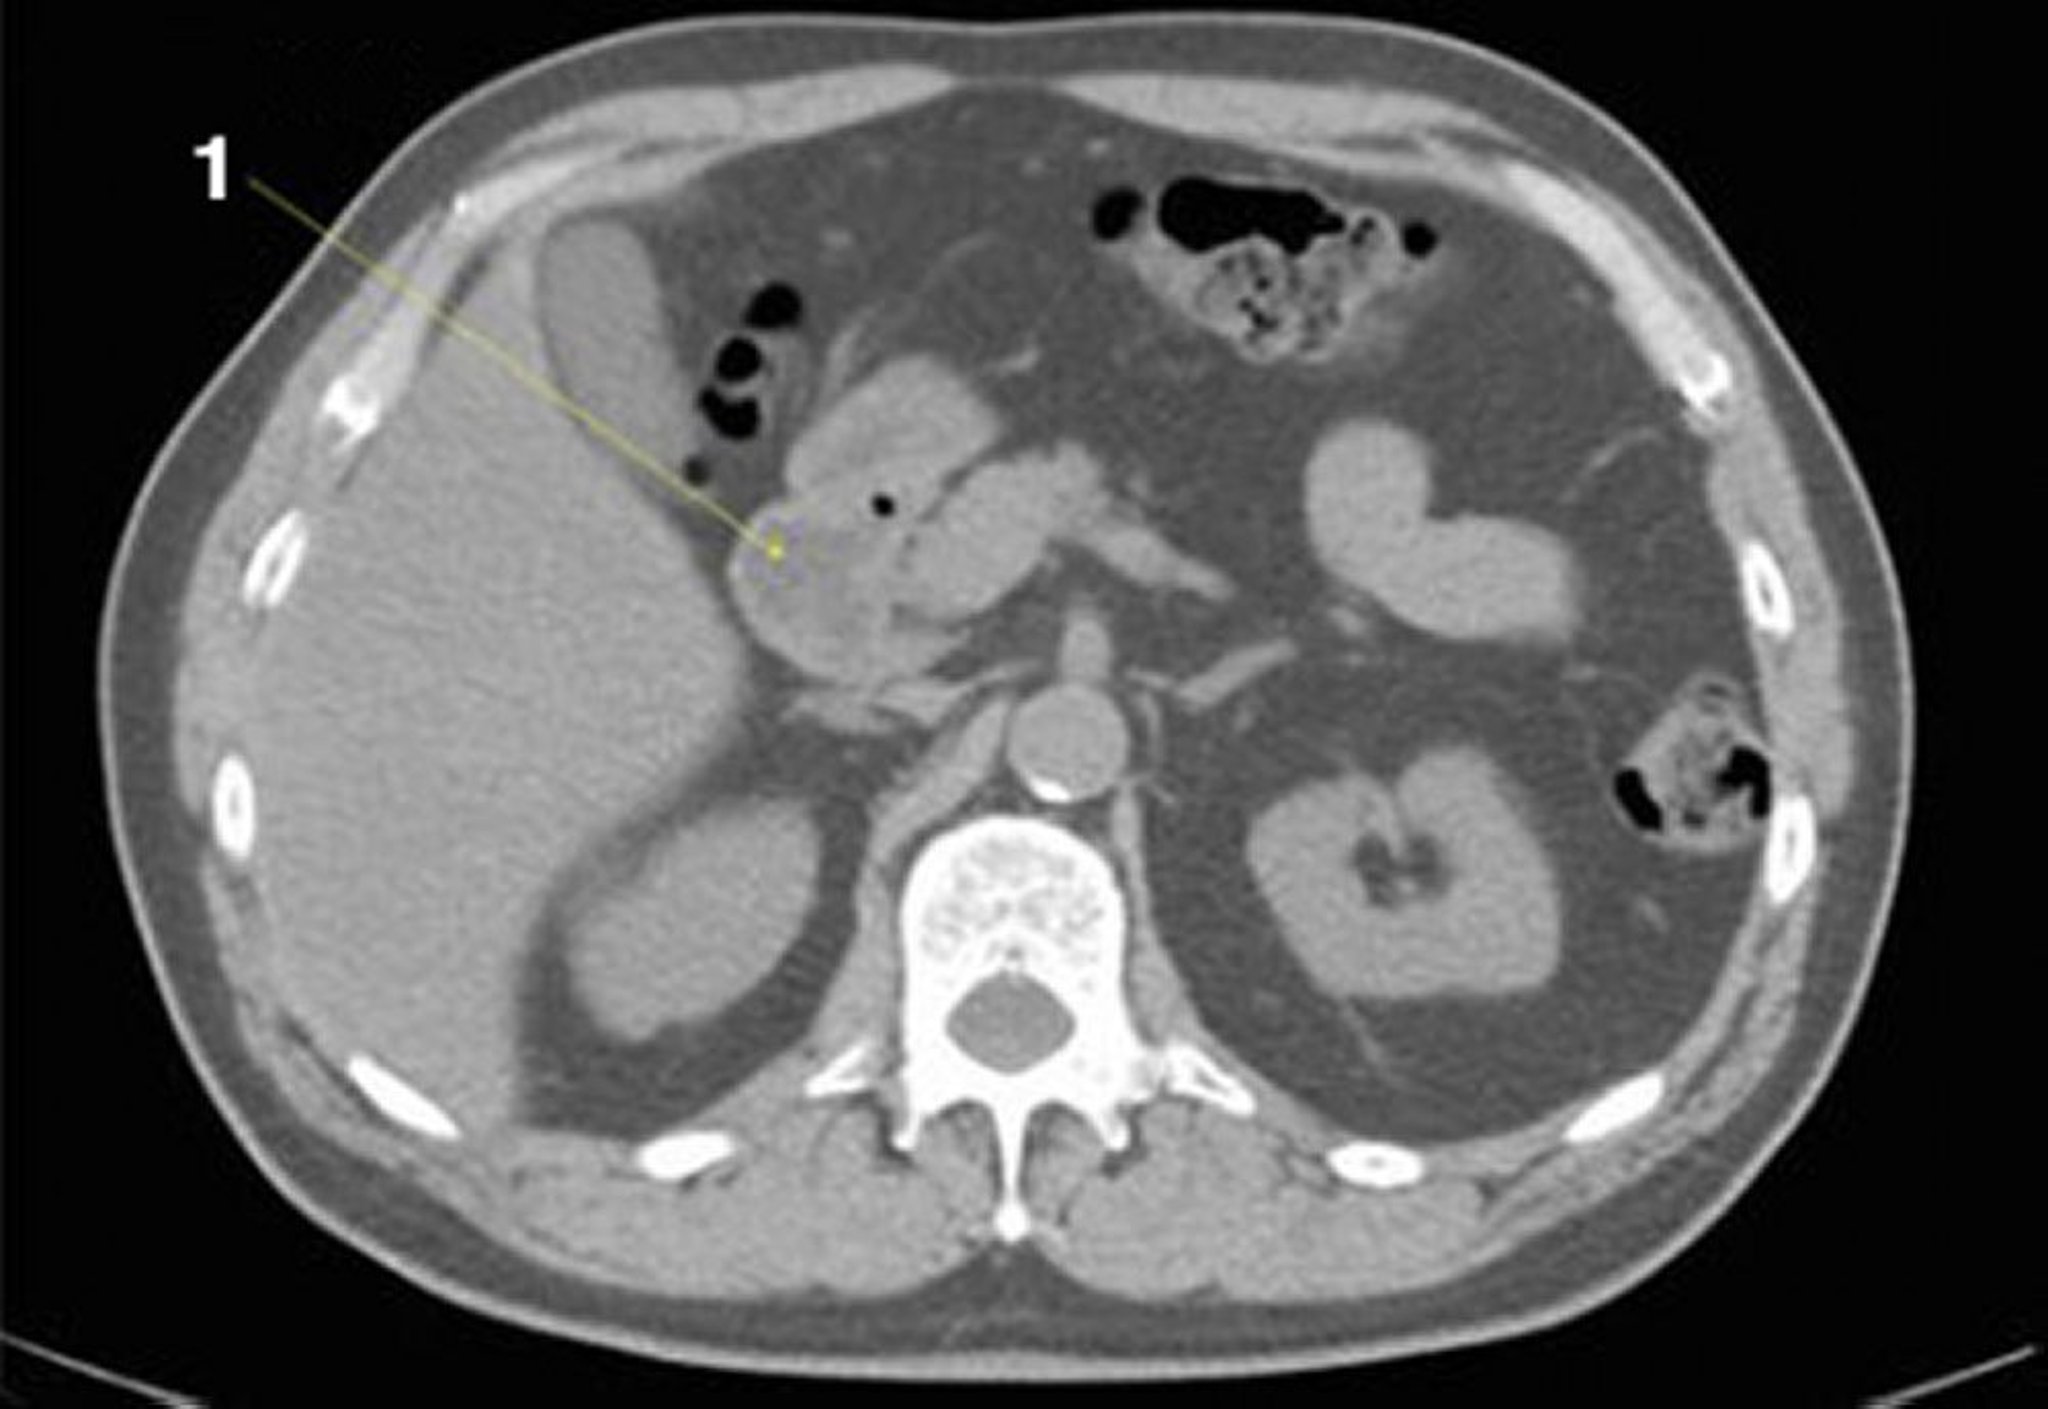

TDM sans contraste de l'abdomen et du bassin montrant une anatomie normale (diapositive 11)

1 = duodénum.